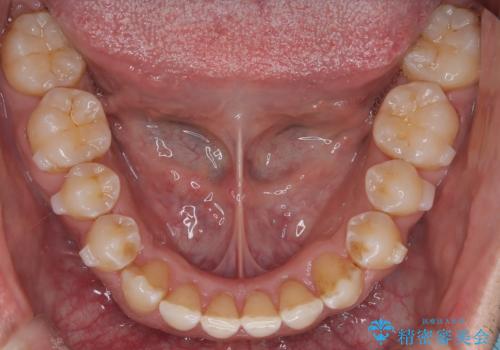

- 左上の八重歯を気にされて来院されました。精密な検査の結果、歯列全体を広げながら八重歯を奥へ移動させることで、美しい歯並びと機能的な咬み合わせが得られると診断。患者様のご希望に合わせ、透明で目立ちにくい**インビザライン(マウスピース矯正)**による治療計画を立案しました。抜歯を避け、歯を少しずつ遠心(奥)へ移動させることで、歯が並ぶスペースを確保し、叢生(歯のデコボコ)を改善します。

今回の矯正治療では、透明なマウスピース型の装置インビザラインを使用しました。この装置は目立ちにくく、取り外しが可能なため、食事や歯磨きも普段通りに行えます。遠心移動という方法で奥歯を後方に動かし、前歯を並べるためのスペースを確保。これにより、抜歯することなく、左上の八重歯を含む叢生を効果的に改善し、整った美しい歯並びと良好な咬み合わせを獲得していただけました。